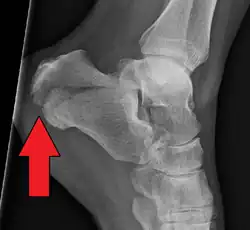

Conventional radiography is usually the initial assessment tool when a calcaneal fracture is suspected. Recommended x-ray views are (a) axial, (b) anteroposterior, (c) oblique and (d) views with dorsiflexion and internal rotation of the foot. However, conventional radiography is limited for visualization of calcaneal anatomy, especially at the subtalar joint. A CT scan is currently the imaging study of choice for evaluating calcaneal injury and has substituted conventional radiography in the classification of calcaneal fractures.[13] Axial and coronal views are obtained for proper visualization of the calcaneus, subtalar, calcaneocuboid and talonavicular joints.

Calcaneal fractures are categorized as intra-articular or extra-articular on the basis of subtalar joint involvement. Intra-articular fractures are more common and involve the posterior talar articular facet of the calcaneus. The Sanders classification groups these fractures into four types based on the location of the fracture at the posterior articular surface. Extra-articular fractures are less common and may be located anywhere outside the subtalar joint.[13] Extra-articular fractures are categorized depending on whether the involvement of the calcaneus is anterior (Type A), middle (Type B) or posterior (Type C).[15]

The Angle of Gissane, or "Critical Angle", is the angle formed by the downward and upward slopes of the calcaneal superior surface. On a lateral radiograph, an angle of Gissane > 130° suggests fracture of the posterior subtalar joint surface. Böhler's angle, or the "Tuber Angle", is another normal anatomic landmark seen in lateral radiographs. It is formed by the intersection of 1) a line from the highest point of the posterior articular facet to the highest point of the posterior tuberosity, and 2) a line from the former to the highest point on the anterior articular facet. Böhler's angle is normally 25° to 40°.[14] It is named after Austrian physician Lorenz Böhler.[16] A decreased angle is indicative of a calcaneal fracture.